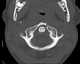

Posterior arch of atlas defect